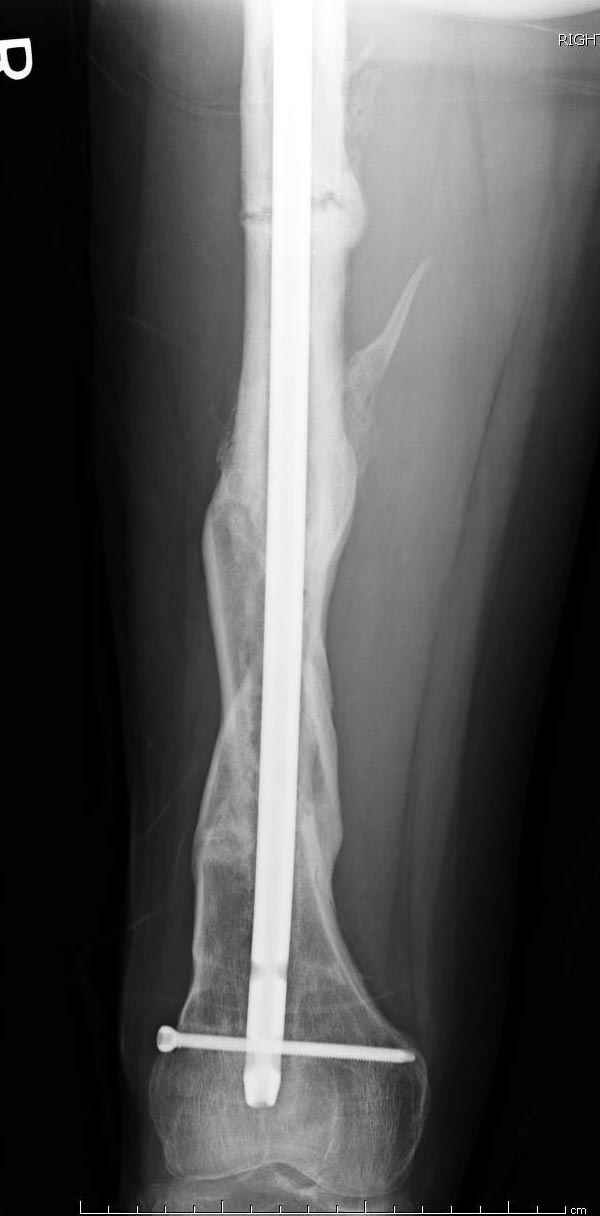

На следующий день произвели интрамедуллярный остеосинтез: этапы во время операции (рис №8, №9)

и последующих снимках (рис №10, 11, 12, 13) перелом сростается и передвигается с полной нагрузкой.